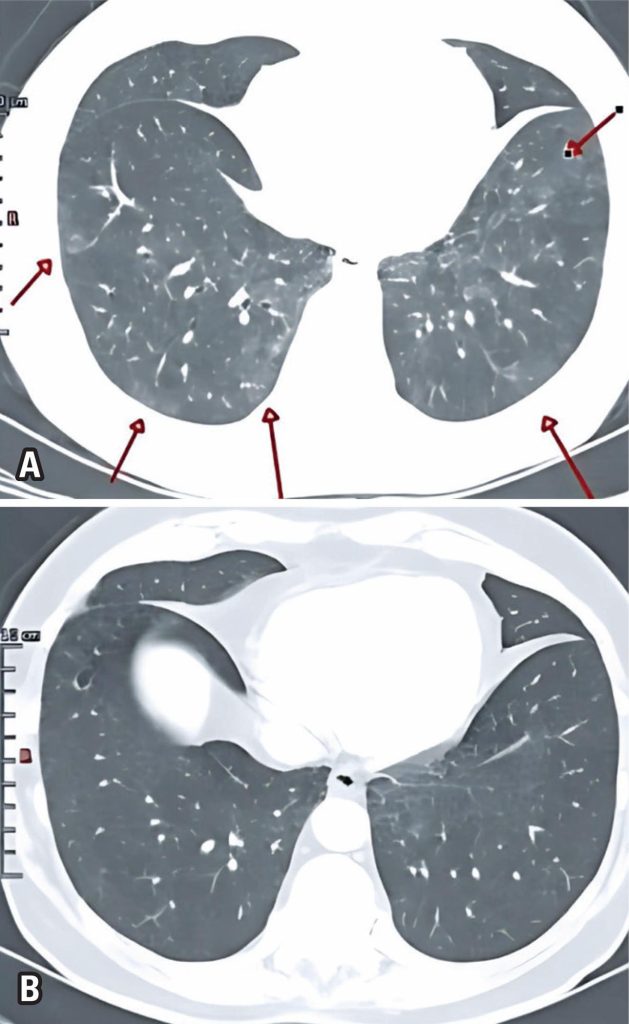

Hypersensitivity pneumonitis is an inflammatory lung disease caused by antigen inhalation after sensitization. Here, we report a rare case of the simultaneous diagnosis of hypersensitivity pneumonitis and epithelioid mesothelioma, a subtype of malignant mesothelioma. A 71-year-old man presented with an occasional dry cough and exertional dyspnea that had persisted for about 1 year. He reported walking daily in a park with a considerable number of birds during same period. Functional evaluation revealed a mild restrictive ventilatory disorder. High-resolution computed tomography showed nonspecific peripheral interstitial lung involvement along with signs of bronchopathy and diffuse bronchiolopath without honeycombing or bronchiectasis. Owing to the patient’s clinical history and the presence of a restrictive ventilatory disorder, a biopsy was performed for diagnostic clarification. Pathological examination revealed hypersensitive pneumonitis associated with epithelioid mesothelioma. Surgical resection of the mesothelioma and avoidance of occupational exposure resulted in complete regression of symptoms and improvement in radiological findings. A report on this rare concomitant diagnosis of the hypersensitivity pneumonitis and epithelioid mesothelioma is essential for advancements in medicine.